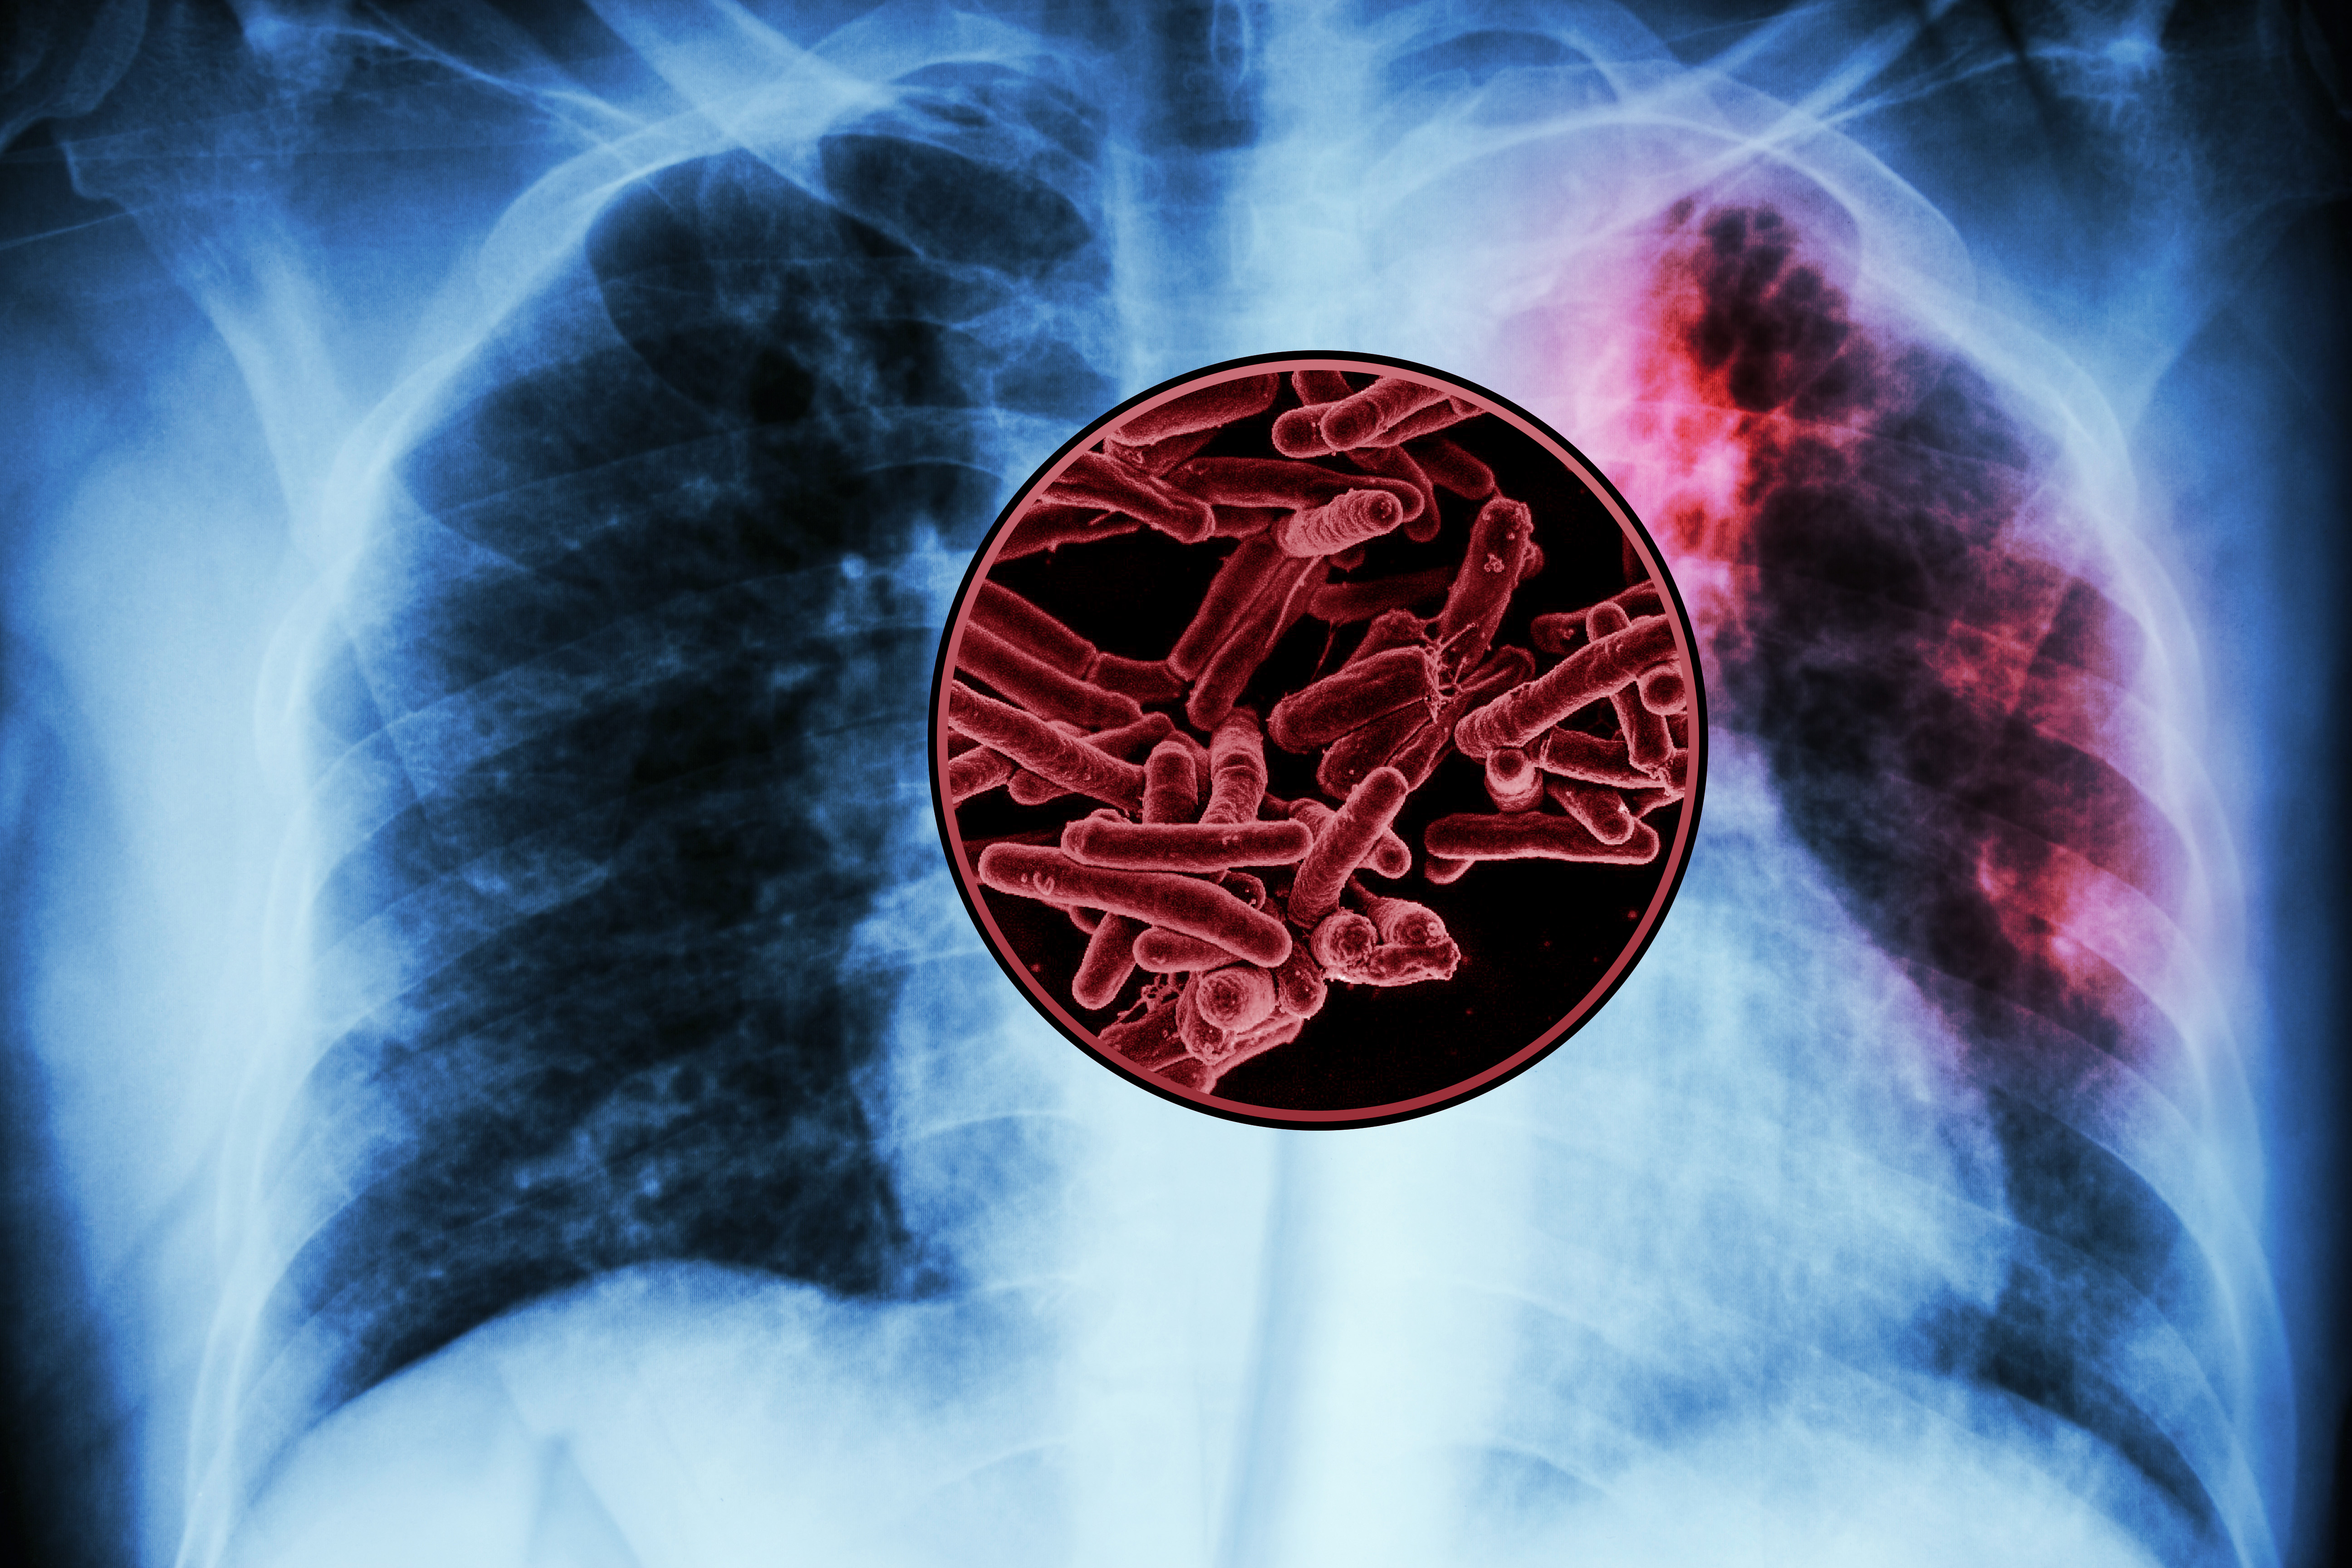

Tuberculosis infected lungs with a close up of tuberculosis bacteria

Caption:

In a new study, a team of MIT biological engineers have identified several possible antigens that could be developed as a new vaccine for TB, the world’s deadliest infectious disease.

Credits:

Credit: NIH-NIAID; iStock; MIT News